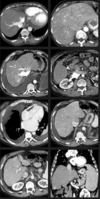

As lesões focais hepáticas na imagem são suspeitas para metástases.

Sequências GRE em fase/fora de fase.

Falso.

As lesões na imagem correspondem a esteatose multifocal/multinodular.